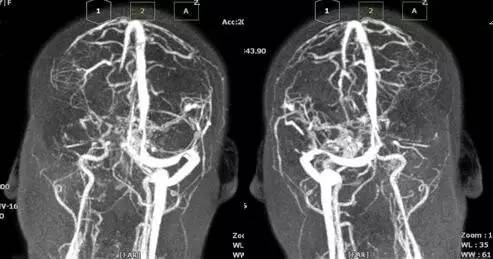

诊治经过:考虑存脑疝,予开颅血肿清除+去骨瓣减压术,,术后予降颅压对症治疗。考虑患者可能存颅内静脉窦血栓,行MRV及全颈脑血管造影术,示“左侧横窦闭塞 矢状窦、右侧横窦血栓形成”。予华法林抗凝治疗。出院PT-INR:2.11。门诊随访中。

▼影像资料